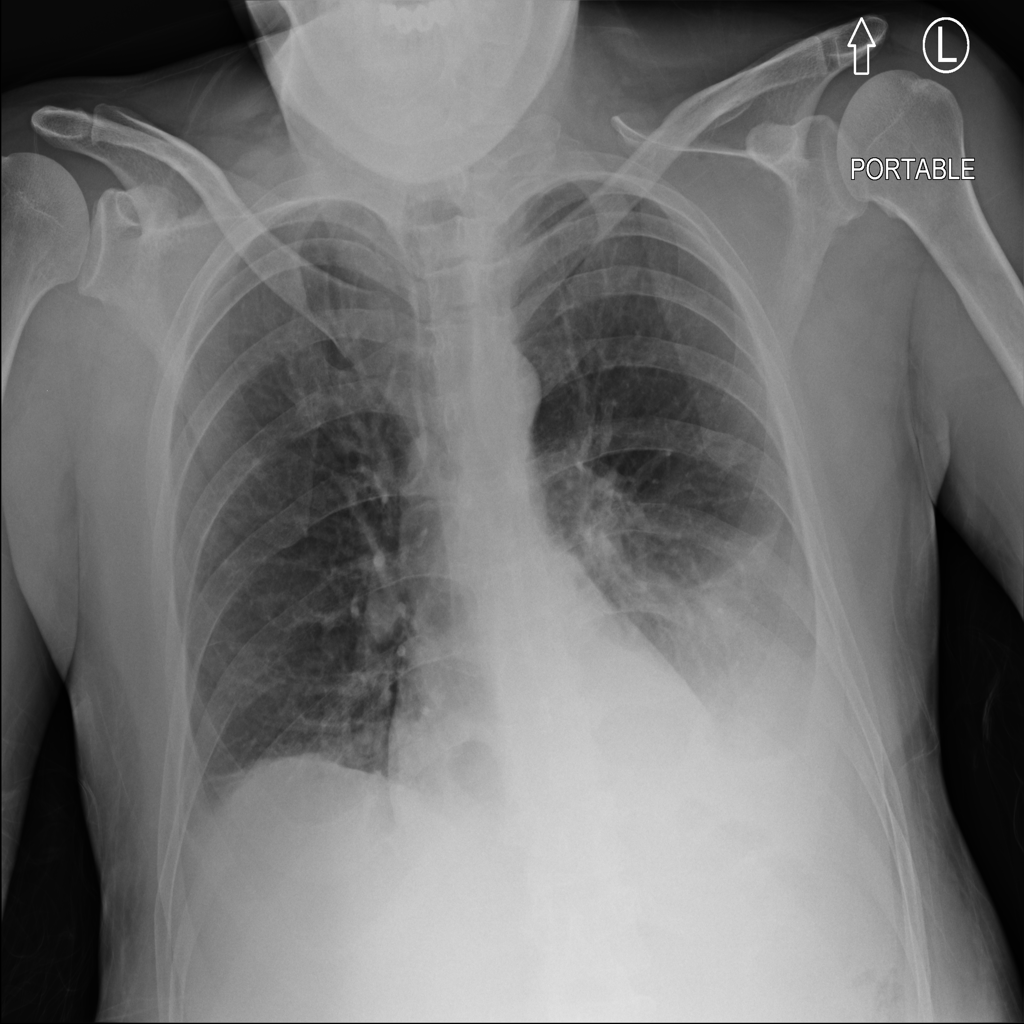

PAT-C1A7 · IMG-004Consolidation

PAT-C1A7 · IMG-004

PA